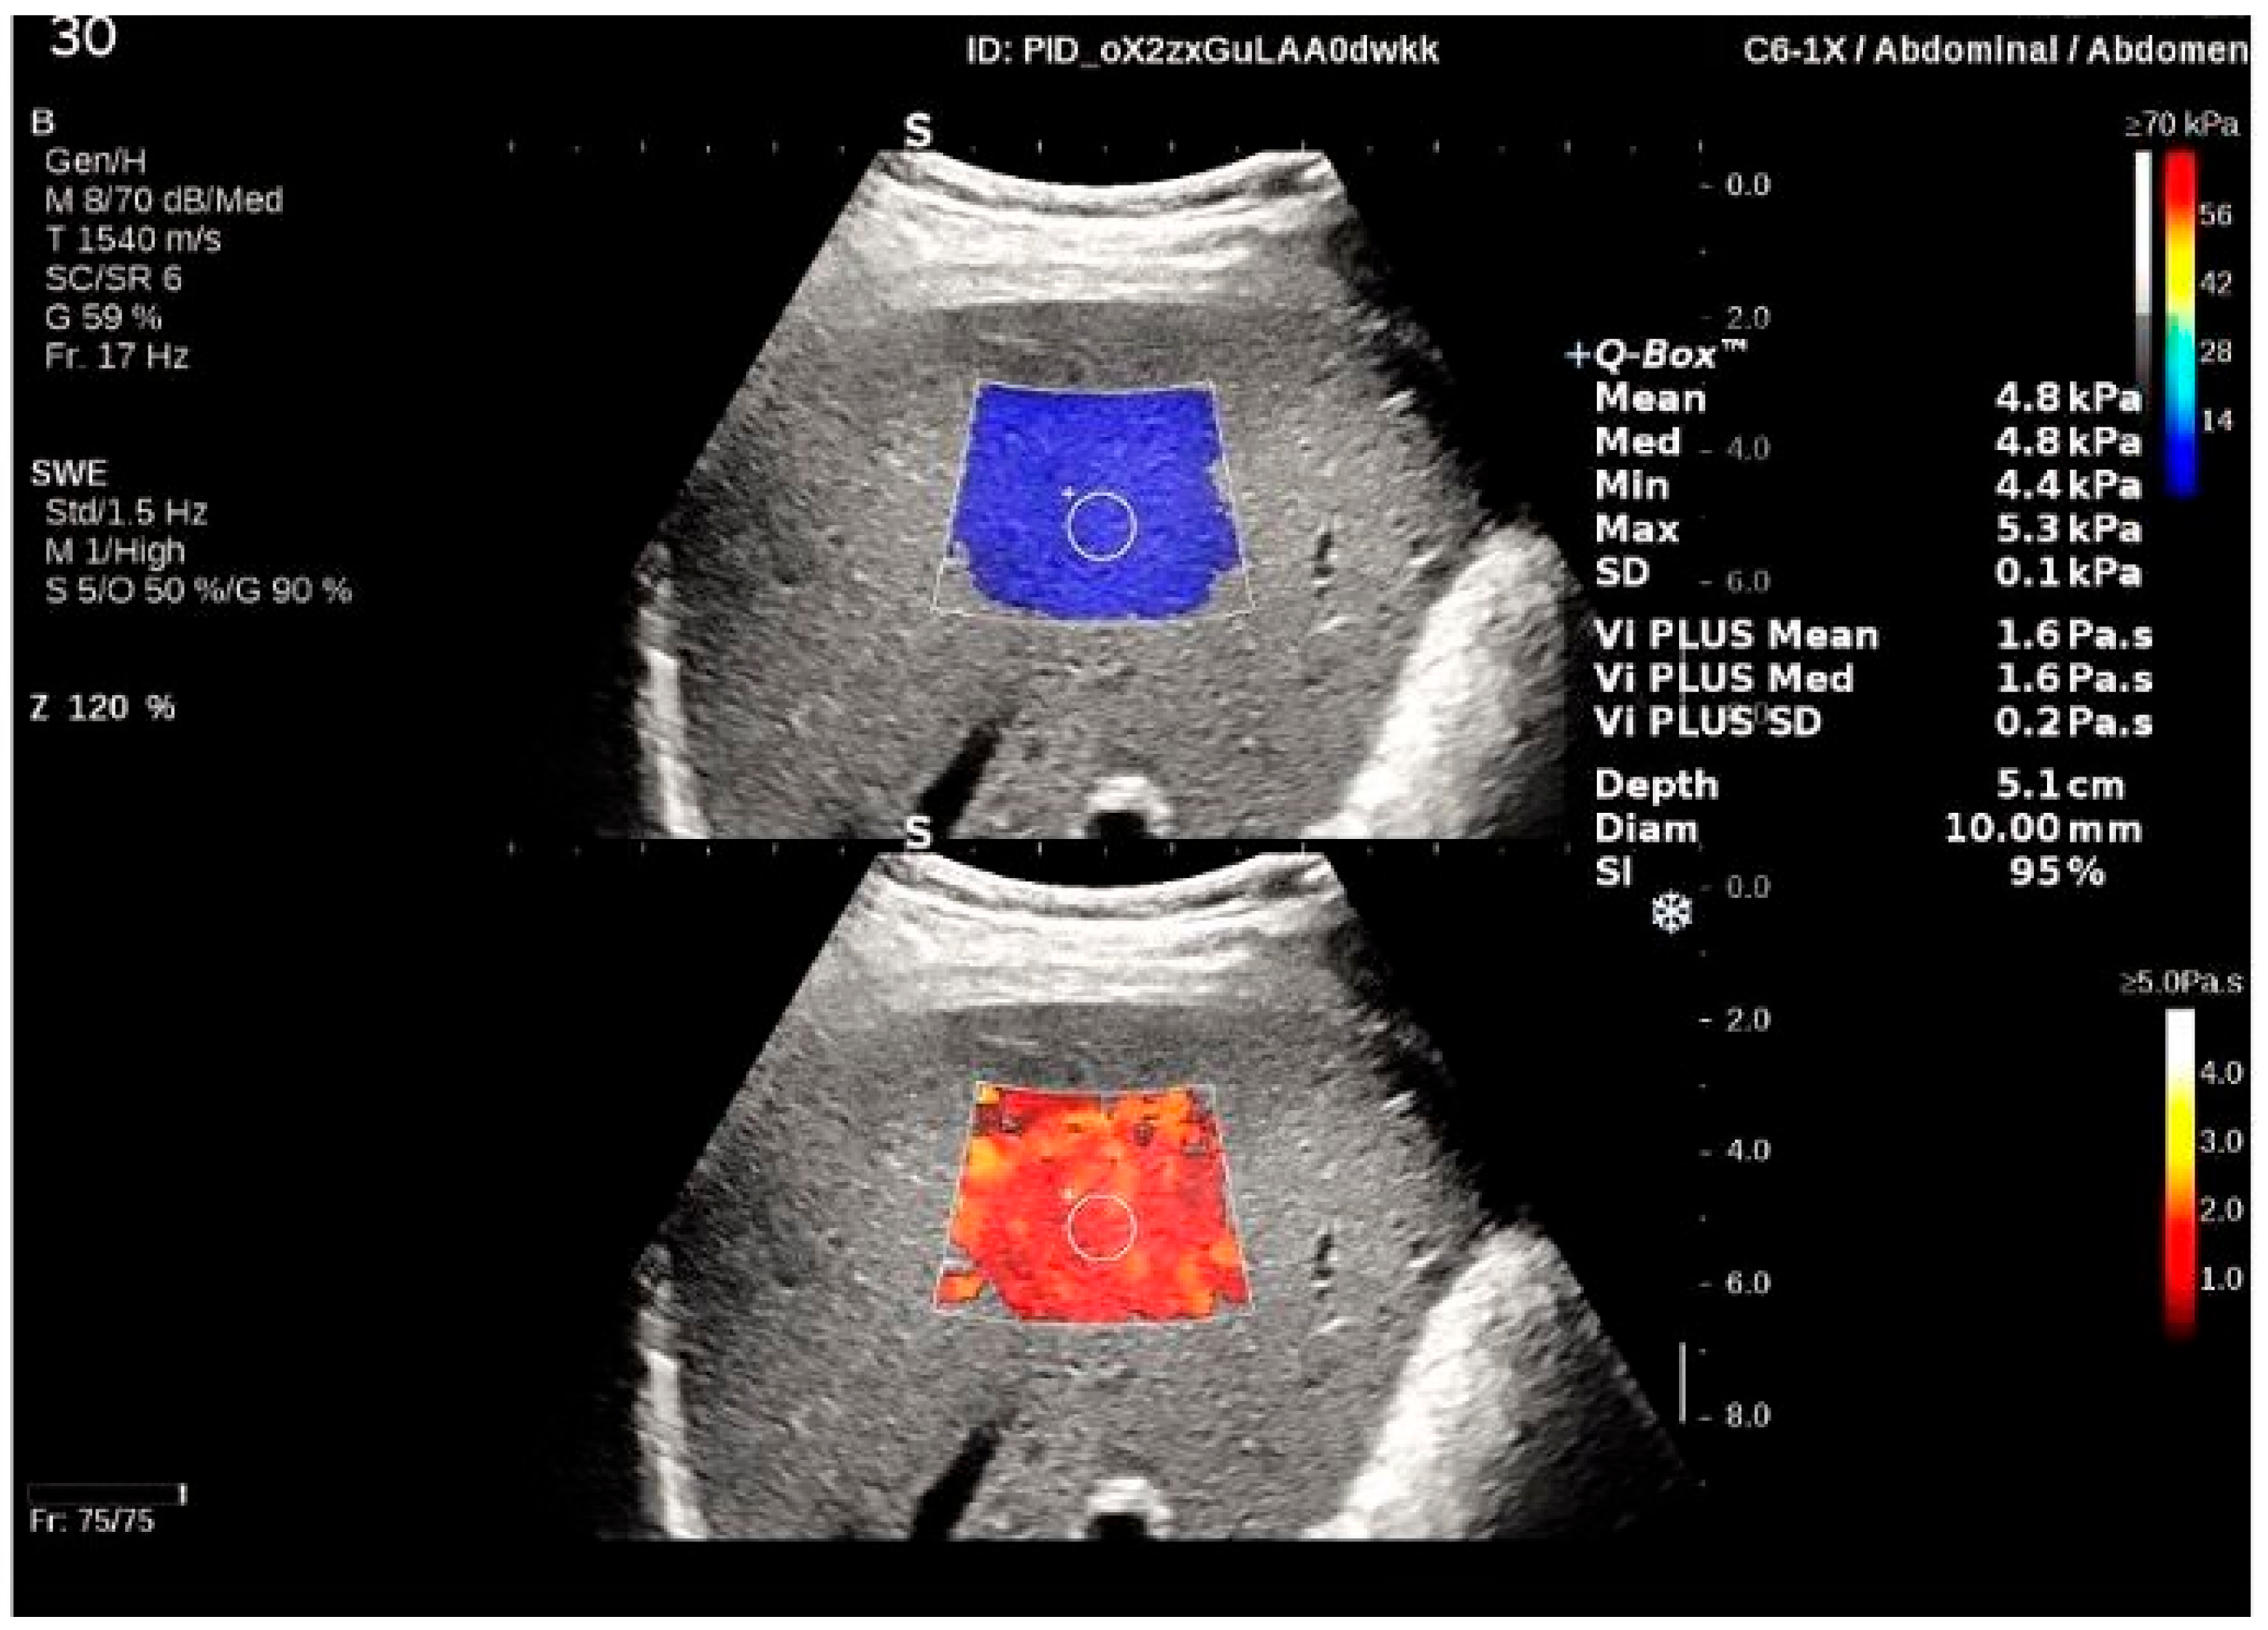

2.5. Viscosity PLUS

| 2D-SWE (kPa) | 4.98 ± 0.99 |

| Vi PLUS (Pa·s) | 1.59 ± 0.20 |